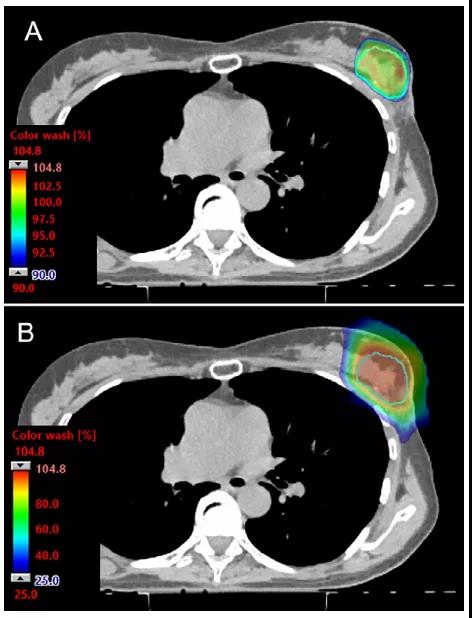

Mayo Clinic報道了76例接受質子筆形束掃描APBI治療患者的早期結果。筆形束掃描因為其限制皮膚表面劑量的能力,進而可以限制急性和晚期皮膚毒性反應的風險(圖3),使得其具有一定的吸引力。在該項研究中,治療分次數(shù)為3次,單次劑量為7.3 Gy(RBE),計劃平均射野數(shù)為2個,采用筆形束掃描技術。1 cm3皮膚體積(定義為體表以下的前3 mm)的最大劑量中位數(shù)為處方劑量的89%。心臟平均劑量中位數(shù)為0.0 Gy(RBE),接受50%及以上處方劑量的同側乳腺體積中位數(shù)為28%。中位隨訪時間12個月,到目前為止,無≥2級急性皮膚毒性反應,無≥2級晚期不良事件。進一步的隨訪將是必要的,以評估該方法的后期效果和長期美容結果。總而言之,鑒于這些前瞻性臨床結果顯示了質子治療與其他APBI替代方案相比的安全性和有效性,質子治療是實施APBI的一個有吸引力的選擇。

圖3. PBS質子治療APBI劑量分布圖。(A)90%的劑量分布顯示了PBS技術實現(xiàn)了高度的劑量適形性和皮膚保護特性。(B)在同一層面下,25%的劑量分布顯示了包括靶區(qū)外乳腺組織在內的良好的正常組織保護。